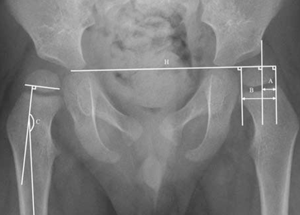

El ACD se obtiene midiendo el ángulo medial entre una línea perpendicular a la epífisis femoral proximal y una línea a través del medio de la diáfisis femoral, de acuerdo a Southwick18. El porcentaje de migración de la cabeza femoral se midió según el método de Reimers4) (figura 1). Dado que la confiabilidad inter e intraobservador es excelente para el ACD con un coeficiente de correlación intraclase (CCI) de 0,92 (95% intervalo de confianza (IC) y un CCI 0,99 (95% IC 0,98-0,99)19 y la confiabilidad inter e intraobservador del PM es alta (CCI=0,93; 95% IC 0,91-0,95)20, la medición fue realizada por un único examinador21. En relación con el cálculo de CPUP Score17, este se realizó a través de la aplicación para dispositivos móviles, y se introdujeron manualmente los datos solicitados (GMFCS, edad, valor de PM y ACD) para cada cadera evaluada, arrojando como resultado el riesgo de progresión de migración expresado en porcentaje. Este score posee una alta habilidad predictiva para diferenciar entre riesgo alto y bajo (área bajo la curva de características del operador receptor = 0,87).

Figura 1: Radiografía frente (F) de pelvis. Cadera derecha: ángulo cérvico-diafisiario (C) midiendo el ángulo interno entre una línea perpendicular a la epífisis proximal de fémur y una línea a través de la diáfisis femoral. Cadera izquierda: porcentaje de migración (PM) medido por una línea de Hilgenreiner (H) y tres líneas perpendiculares, utilizando A/B x 100%. Imagen tomada de Van der List, et al. J Child Orthop (2015) 9:129-35.